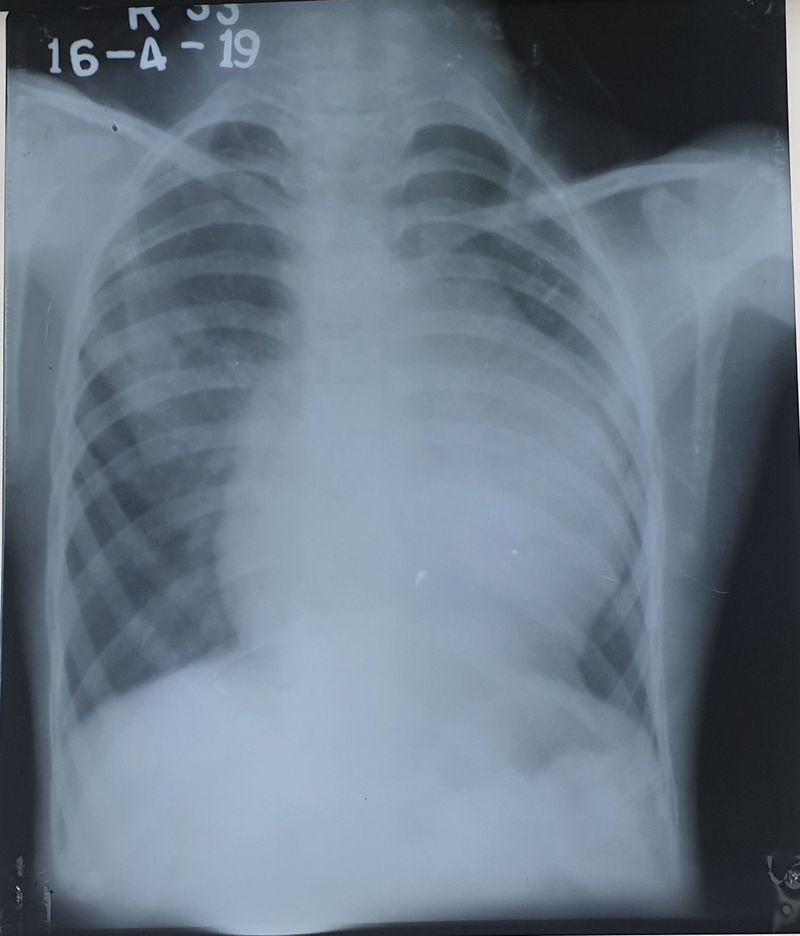

What's your diagnose ?

A patient age 12 year old male patient come with C/o of weakness weight lose , with anorexia i recommended for chest x-ray now i found this? Cardio megaly .

CXR - Ebstein anomaly

Does he have cyanosis too?

No he have not